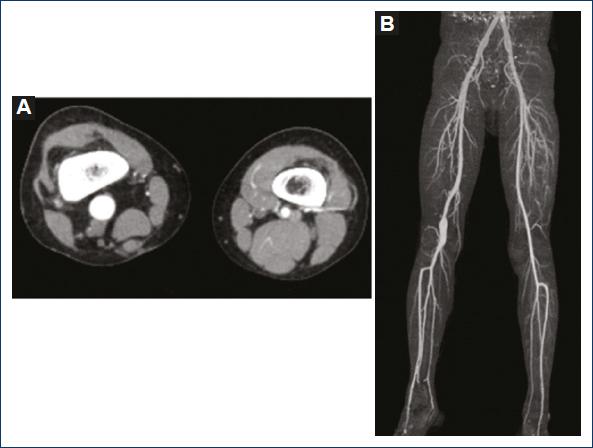

At 5 years of age, patient underwent another CTA, confirming the existence of popliteal aneurysm, without significant variations in the size of the aneurysm described (Fig. 1); the patient was admitted to the institution referred by his attending physician, who reported an increase in the perimeter of the limb involved in the previous year. Physical examination revealed a congestive, purplish-colored right lower limb with increased circumference, distal pulses present, popliteal pulse more evident than the left, with no gait disturbance, or intermittent claudication (Fig. 2).

Figure 1 A: computed tomography angiography (CTA) of lower limbs, cross-section showing difference in diameters between the right popliteal artery and the normal left popliteal artery. B: 3D reconstruction of lower limb - CTA.